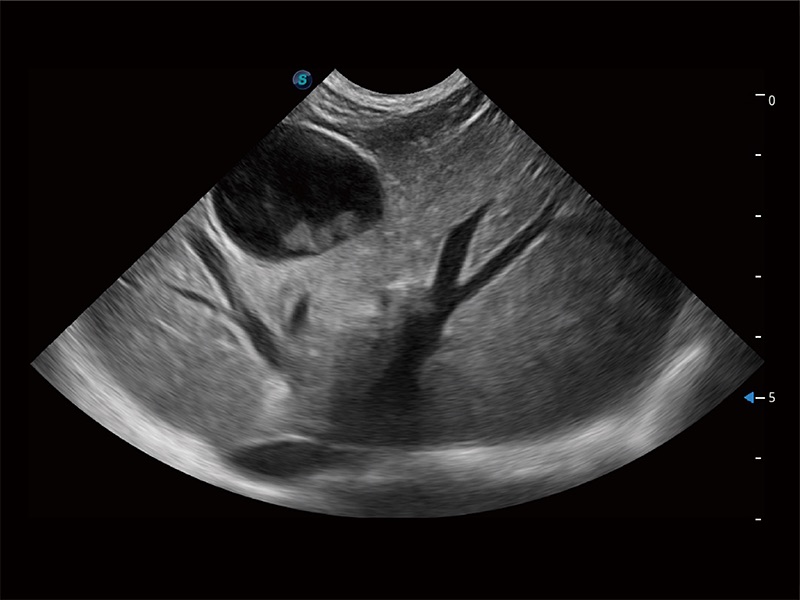

优异的基础图像

ProPet 80 全新的动物超声智能软件和丰富的探头群,为动物医生提供了高清晰度和精细分辨率的图像,无论在宠物、马科、畜牧还是实验室动物等应用中都可以轻松应对,为您的日常工作带来满意的体验。

(犬)四腔心MQA

(猫)二尖瓣M型

(犬)二腔心血流